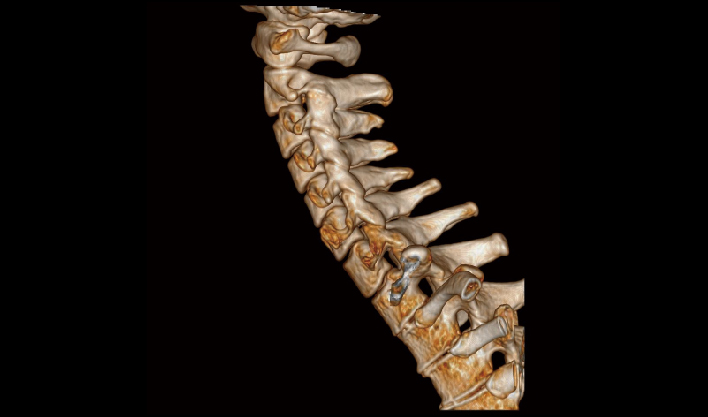

La matriz de reconstrucción de 1024*1024 amplía los datos de la imagen cuatro veces. Combinado con imágenes de corte fina, incluso las lesiones más invisibles son claramente visibles.